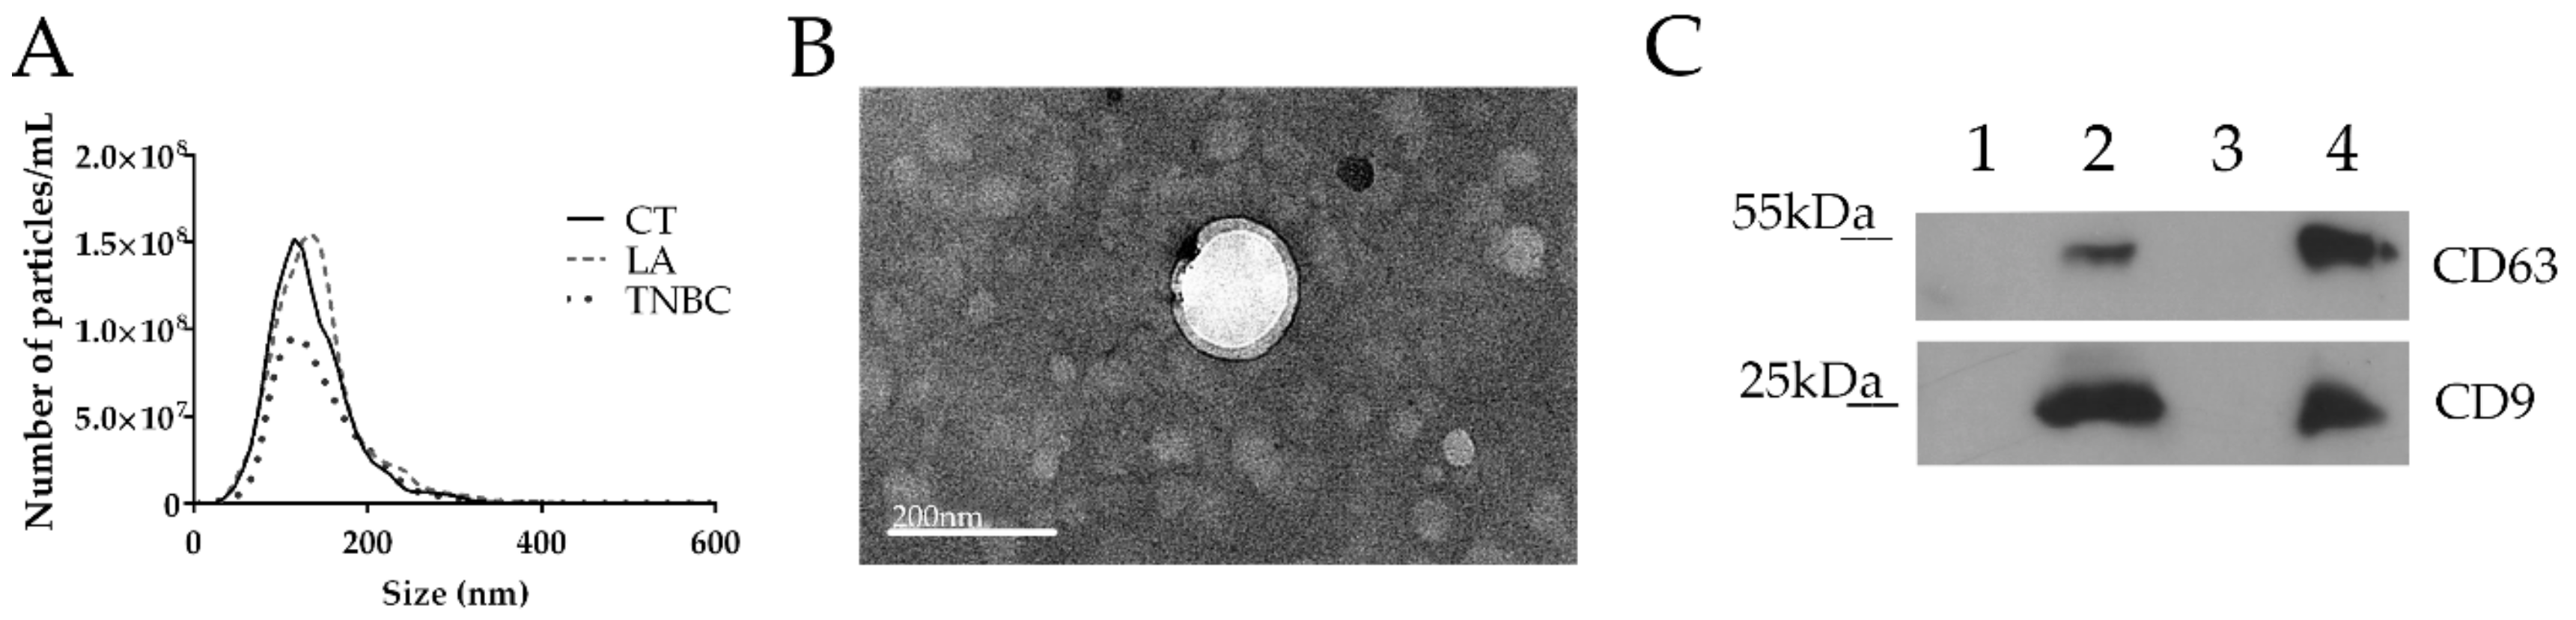

3.1. EVs’ Isolation and Characterization